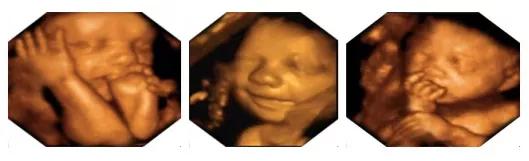

新手妈妈必须知道的产前超声筛查